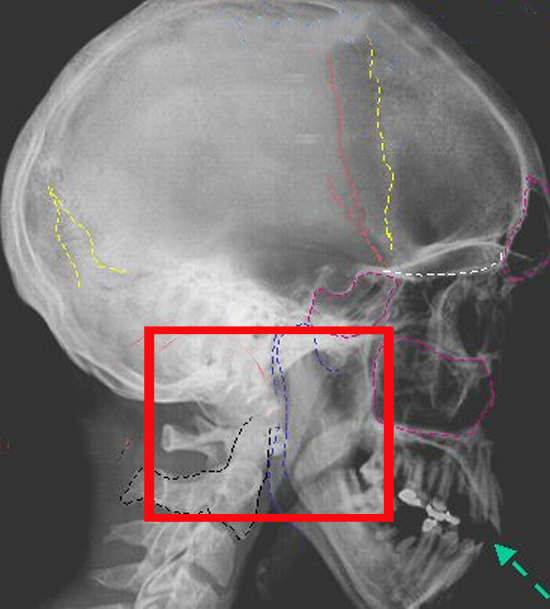

Переломы черепа, как и остальных костей можно разделить на закрытые и открытые переломы черепа и, по характеру их можно разделить на дырчатые, вдавленные, оскольчатые и линейные.

Линейный перелом черепа

Линейные переломы – это самый удачный случай перелома костей черепа, при котором не происходит их смещения. Поэтому такие переломы редко требуют принятия срочных мер.

Перелом свода черепа

Основными симптомами перелома костей свода черепа являются вдавления, рана или гематома в области части головы, покрытой волосами. Общие проявления перелома свода черепа полностью зависят от степени тяжести перелома и могут варьироваться от потери сознания на момент травмы до глубокой комы, параличей и прочего.

Перелом основания черепа

Черепно-мозговые травмы, прежде всего, опасны из-за своих последствий. Статистика гласит, что среди всех черепно-мозговых травм чаще всего встречается именно перелом основания черепа (от 32-59% пострадавших в зависимости от места сбора статистики).